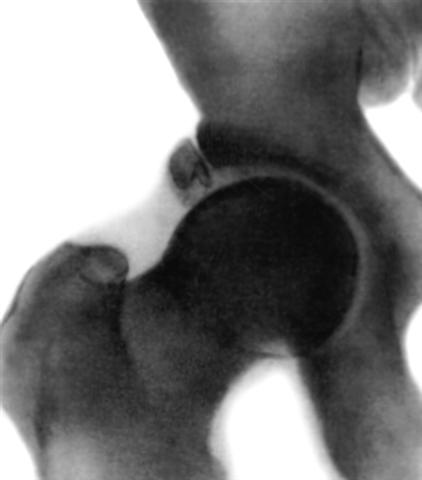

Рис. 6б). Рентгенограмма тазобедренного сустава (прямая проекция) взрослого в норме: у края вертлужной впадины видны добавочные костные образования (неслившиеся ядра окостенения).